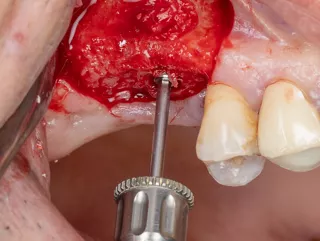

9. Placement of a new collagen sponge to protect the mucosa from the drill holes and start of the implant drilling sequence with the Pointer drill.

10, 11, 12, 13, 14, 15:

Drilling sequence and control of implant axis with gauges corresponding to the diameter of the drills used, all included in the surgical kit Axiom®.

10. Sequential drilling using an initial Ø 2 mm drill, followed by a Ø 2.4 mm drill (green).

14. The last drill used has a Ø 3.0 mm diameter (red), for the placement of Axiom® BL X3 Ø 4.0 mm and 10mm length implant and confirmation of the axis using the adapted gauge.

11. 12. 13. Checking the depth and axis using the gauge.